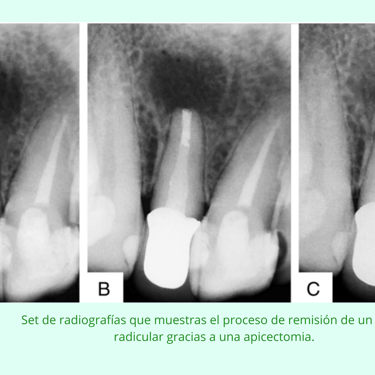

Evaluación Inicial: Examen clínico y radiografías para determinar la necesidad de la apicectomía.

Resultados esperados: Eliminación de la infección crónica y conservación del diente, con una alta tasa de éxito a largo plazo.